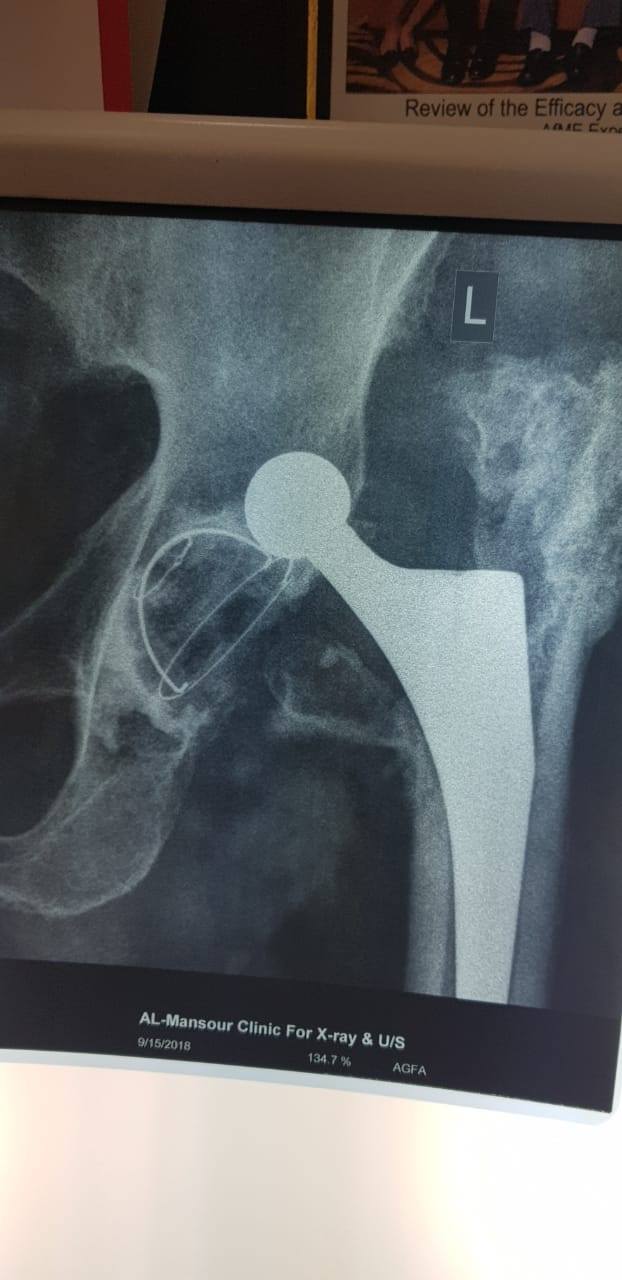

زراعة المفاصل الصناعية ورك و